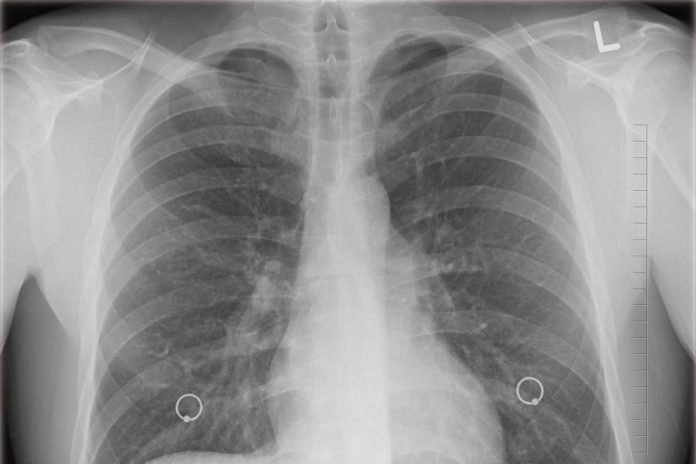

Para descubrirlo, los especialistas midieron los niveles de varias proteínas en las células infectadas de los pulmones y la tráquea de una persona.

Encontraron que la expresión de ACE2 era baja en todas las líneas celulares, pero los científicos descubrieron otra proteína, cuya sobreexpresión en los tejidos del sistema respiratorio facilitó la penetración del Covid-19.